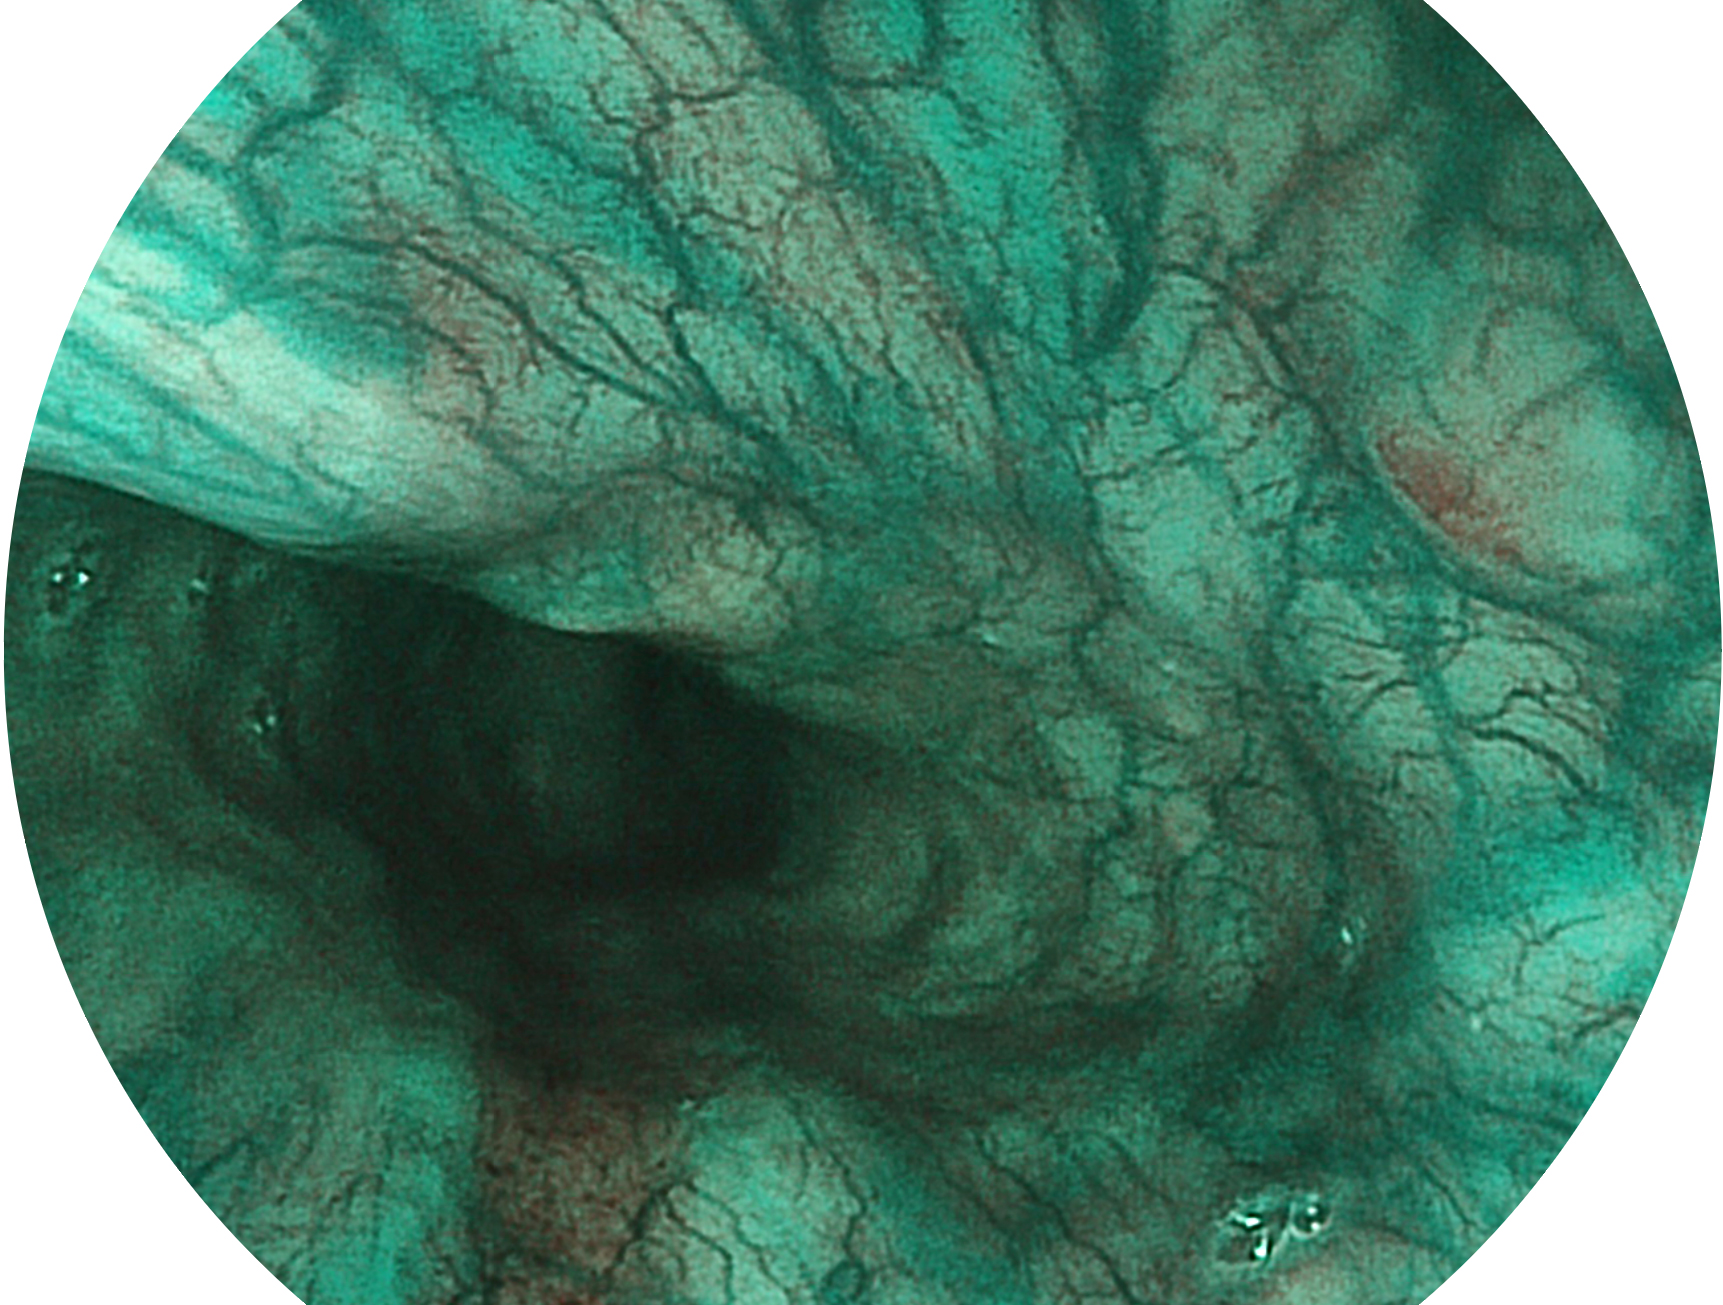

乐玩lewin国际新开发的内镜染色技术,主要是基于多波长LED 光源的开发,VLS-55Q 四波长LED 光源是由四个不同颜色的LED光按照相应照明模式所规定的特定发光比例进行合束后形成,合束后形成的照明光的光谱由红光、绿光、蓝光及蓝紫光这四个不同的波段范围构成。具有更高光谱自由度,通过光谱比例的控制,实现了聚谱成像技术,英文全称为“Spectral Focused Imaging, SFI”,缩写为“SFI”和光电复合染色成像技术,英文全称为“Versatile Intelligent Staining Technology, VIST”,缩写为“VIST”。